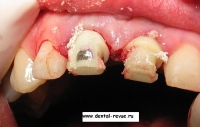

3. Вид до операции.